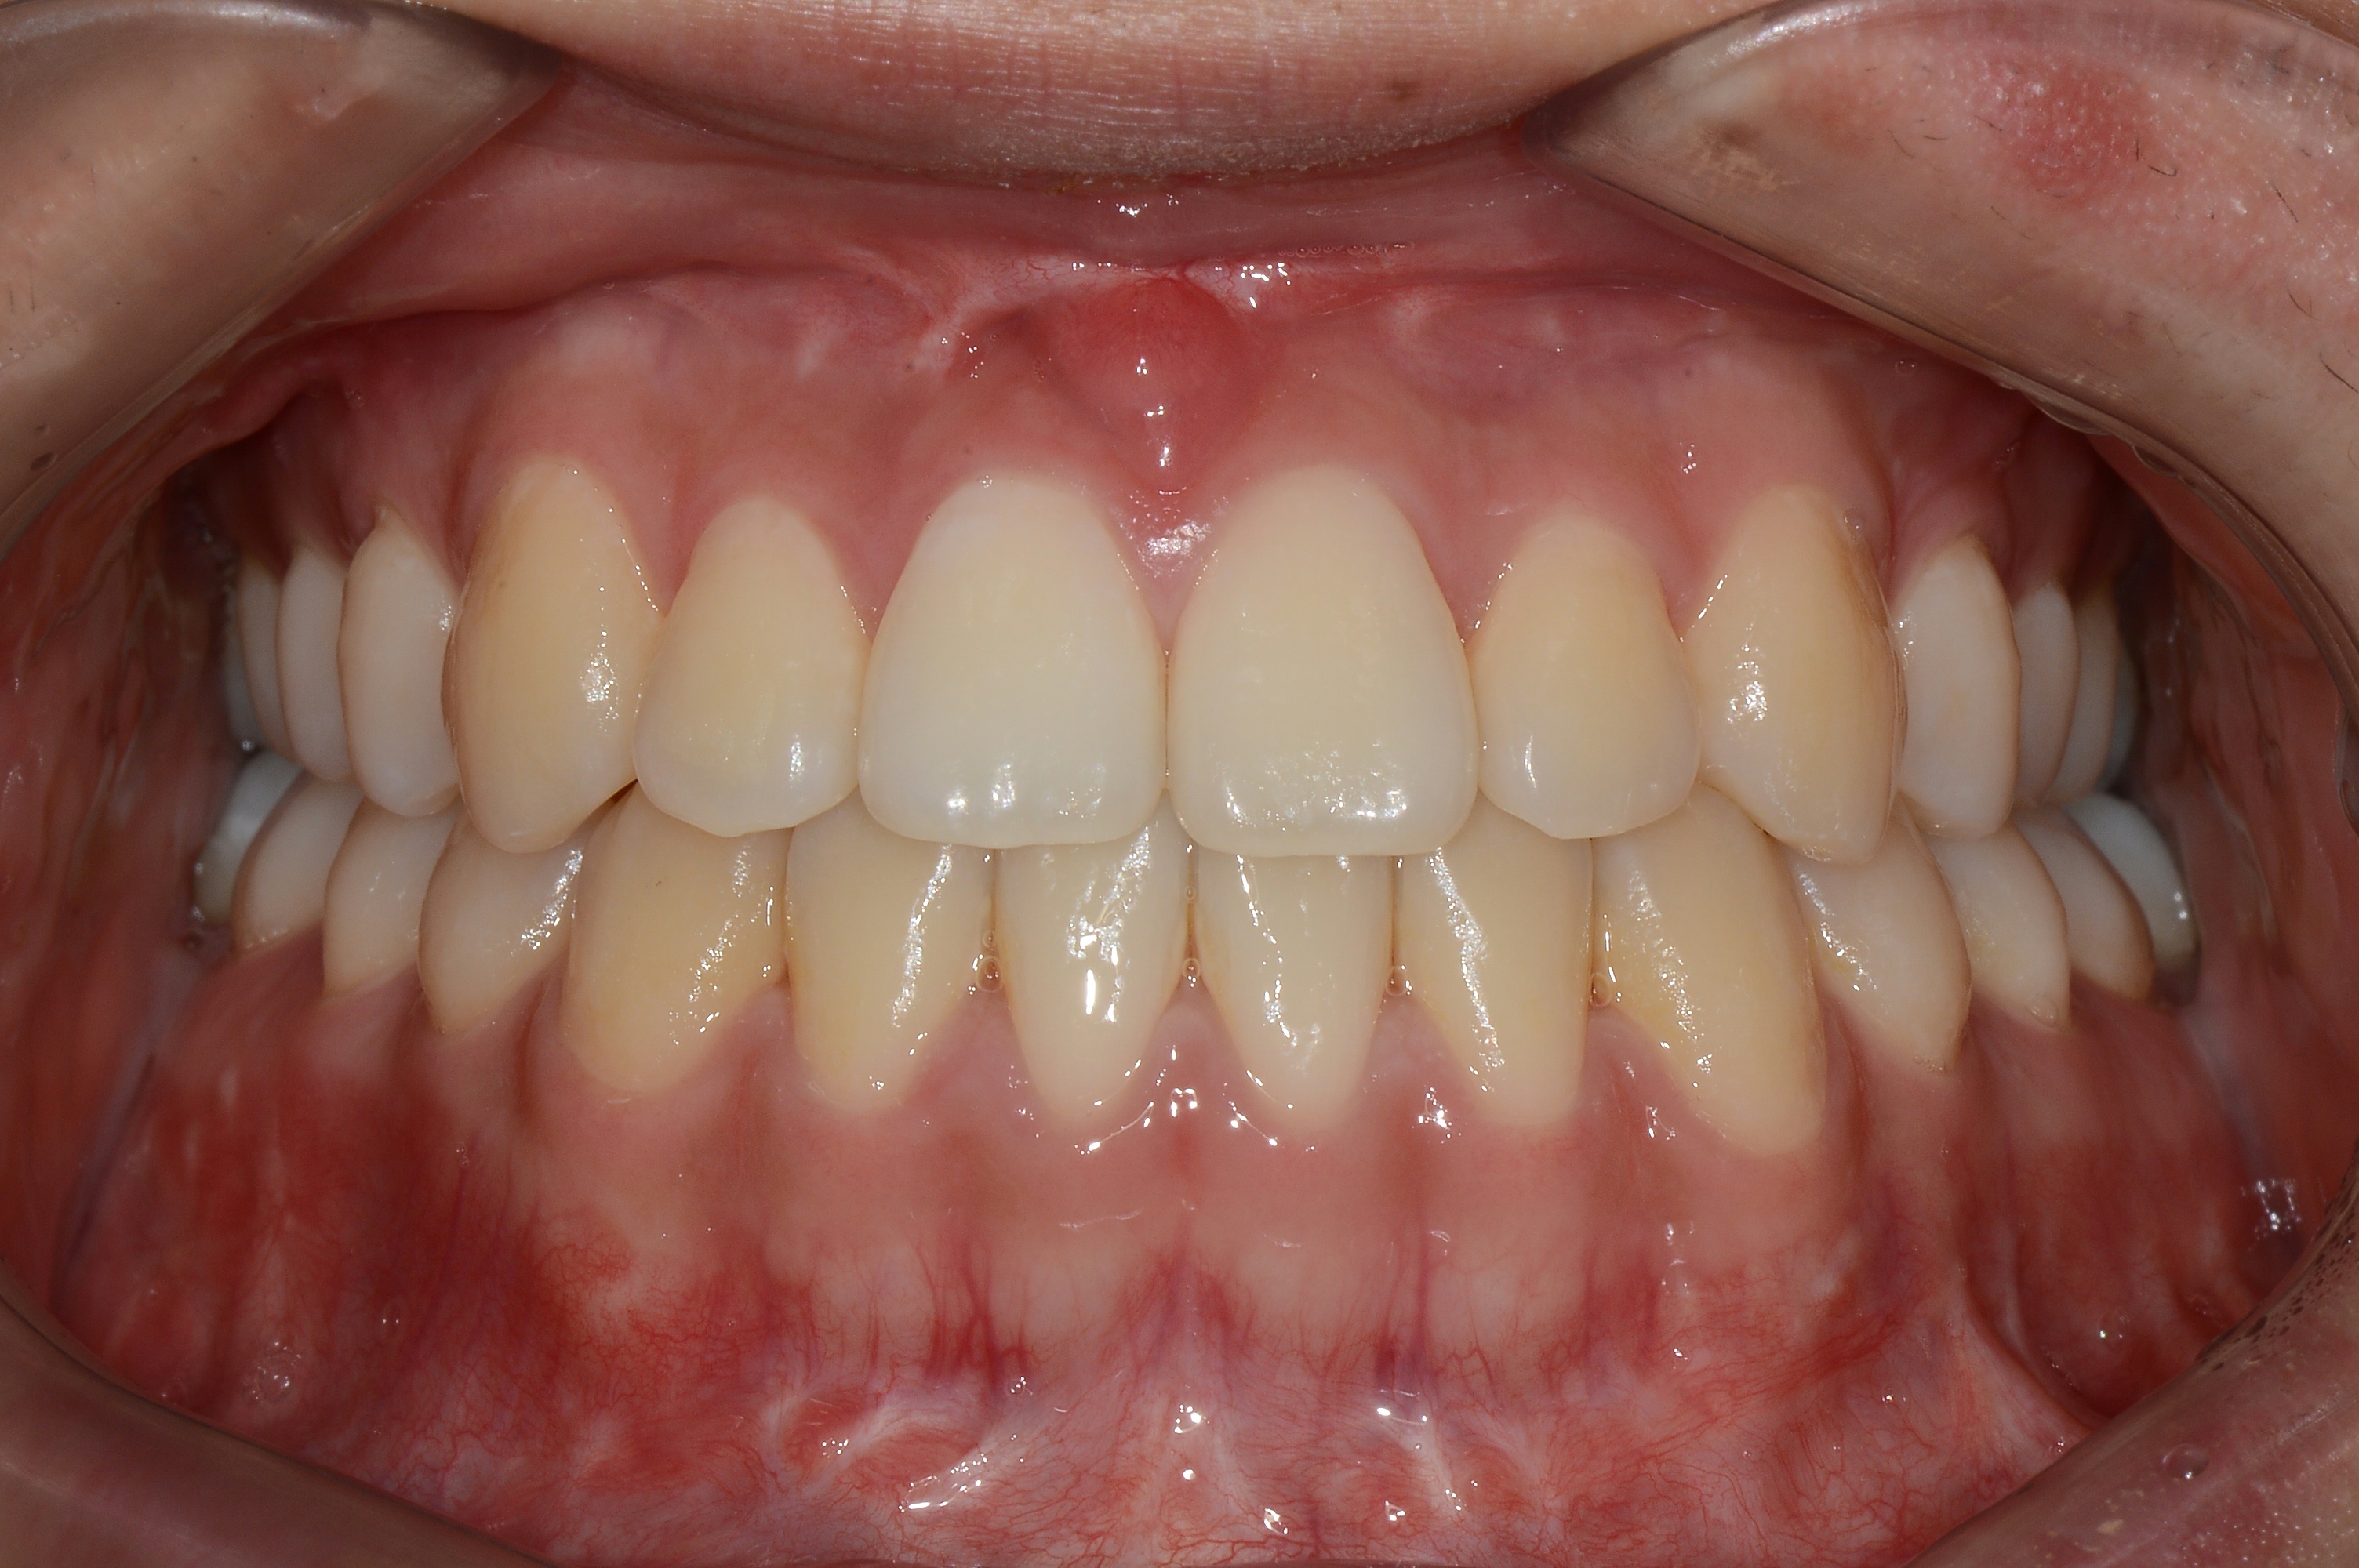

치료 후 사진입니다.